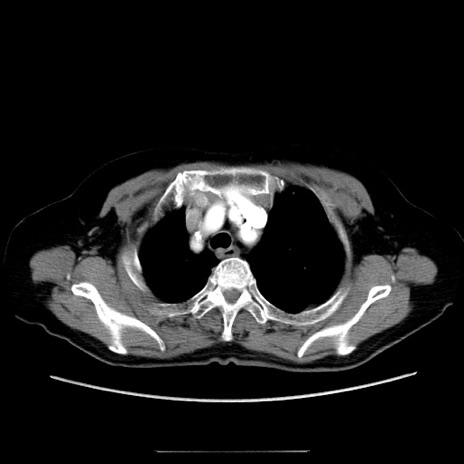

冠状断像

【症例】70歳代女性

【主訴】お腹が張る

【現病歴】1週間くらい前から腹部膨満の自覚あり。昨日夜から増悪したため、本日救急外来受診。

【身体所見】意識清明、BT 36.5℃、BP 165/106mmHg、HR 80bpm、SpO2 98%、腹部:膨満、軟、自発痛・圧痛なし、触診にて不快感あり、腸蠕動音:減弱

【データ】WBC 12600、CRP 1.04